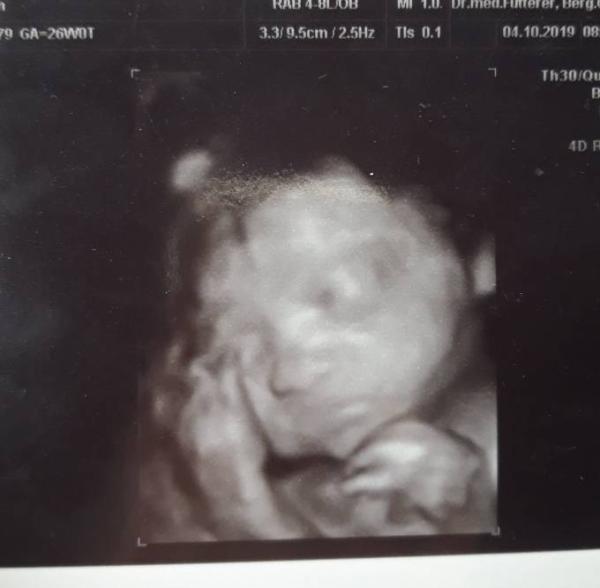

Heute beginnt die 27 Woche und wir hatten unsere nächste Untersuchung. Unsere kleine Sophie wiegt mittlerweile 911g Und ist Kern gesund

Bild zu Ich bin verliebt :D - Forum für Januar - Mamis